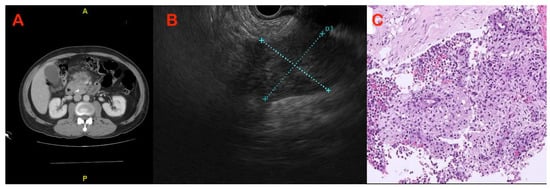

7.1. Paraduodenal or “Groove” Pancreatitis

- Muraki, T.; Kim, G.E.; Reid, M.D.; Mittal, P.; Bedolla, G.; Memis, B.; Pehlivanoglu, B.; Freedman, A.; Seven, I.E.; Choi, H.; et al. Paraduodenal Pan- creatitis: Imaging and Pathologic Correlation of 47 Cases Elucidates Distinct Subtypes and the Factors Involved in its Etiopathogenesis. Am. J. Surg. Pathol. 2017, 41, 1347–1363. [Google Scholar] [CrossRef] [PubMed]

- Arora, A.; Rajesh, S.; Mukund, A.; Patidar, Y.; Thapar, S.; Arora, A.; Bhatia, V. Clinicoradiological appraisal of ‘paraduodenal pancreatitis’: Pancreatitis outside the pancreas! Indian J. Radiol. Imaging. 2015, 25, 303–314. [Google Scholar] [CrossRef] [PubMed]

- Al-Hawary, M.M.; Kaza, R.K.; Azar, S.F.; Ruma, J.A.; Francis, I.R. Mimics of pancreatic ductal adenocarcinoma. Cancer Imaging. 2013, 13, 342–349. [Google Scholar] [CrossRef] [PubMed]